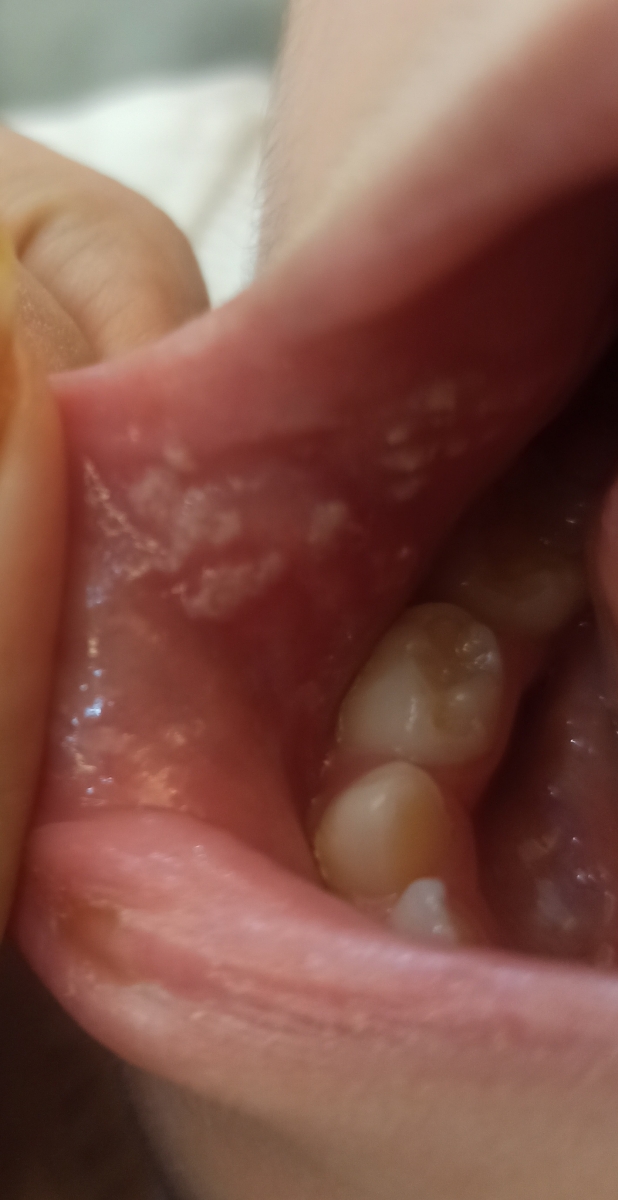

سلام میشه بگید این دونه ها چی هست بعید میدونم آفت باشه

گاز گرفتگی و ساییده شدن هست؟

دونه های سفید چی هست

اینا آفت هست قطره نیستاتین بزنین بهشون

سلام گلم پسر من یه سری تب شدید کرد دقیق همین مدل شد دکتر گفت افت هست قطره نیستاتین تجویز کرد گفت تا جایی که بشه نذار قورت بده ولی خب. پسرم میریخت بیرون

آفته عزیزم نیستاتین بچکون روش

سلام نازنینم

بنظر من برفک هست باید نیستاتین شروع کنید ، هر 6 ساعت مقدار توصیه شده خود محصول را بدهید بخورد ولی به شکلی بدهبد که روی بخش سفید بریزید و بعد بخورد و همچنین با گوش پاک کن روی بخش هتی درگیر بمالید و تا حداقل 10 الی 30 دقیقه بعد استفاده چیزی نخورد